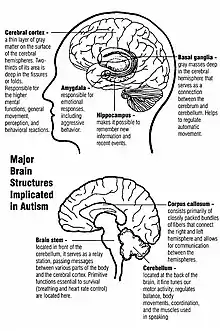

The mechanisms of autism are the molecular and cellular processes believed to cause or contribute to the symptoms of autism. Multiple processes are hypothesized to explain different autism spectrum features. These hypotheses include defects in synapse structure and function,[1][2] reduced synaptic plasticity,[3] disrupted neural circuit function, gut–brain axis dyshomeostasis,[4][5][6] neuroinflammation,[7] and altered brain structure or connectivity.[8][9][10][11]

Pathophysiology

Unlike some brain disorders which have clear molecular hallmarks that can be observed in every affected individual, such as Alzheimer's disease or Parkinson's disease, autism does not have a unifying mechanism at the molecular, cellular, or systems level. The autism spectrum may comprise a small set of disorders that converge on a few common molecular pathways, or it may be a large set of disorders with diverse mechanisms.[13] Autism appears to result from developmental factors that affect many or all functional brain systems.[14] Some factors may disturb the timing of brain development rather than the final product.[12]

Brain growth

Neuroanatomical studies and the association between autism and teratogens strongly suggest that autism affects brain development soon after conception.[15] This anomaly appears to start a cascade of pathological events in the brain that are significantly influenced by environmental factors.[16] Just after birth, the brains of children with autism tend to grow faster than usual, followed by normal or relatively slower growth in childhood.[17] It is unknown whether early brain overgrowth occurs in all children with autism. It appears to be most prominent in the frontal and temporal lobes, which are associated with higher cognitive specializations such as social cognition, and language development.[18] Hypotheses for the cellular and molecular bases of pathological early overgrowth include an excess of neurons that causes local overconnectivity in key brain regions,[17] and disturbed neuronal migration during early gestation.[19][20]

Altered circuit connectivity

The underconnectivity theory of autism posits that autistic people tend to have fewer high-level neural connections and less global synchronization, along with an excess of low-level processes.[27] Functional connectivity studies have found both hypo- and hyperconnectivity in brains of autistic people.[28] Hypoconnectivity is commonly observed for interhemispheric and cortico-cortical functional connectivity.[29] Some studies have found local overconnectivity in the cerebral cortex and weak functional connections between the frontal lobe and the rest of the cortex.[30] Abnormal default mode network (task-negative) connectivity is often observed. Toggling between task-negative network activation and task-positive network activation (consisting of the dorsal attention network and salience network) may be less efficient, possibly reflecting a disturbance of self-referential thought.[31] Such patterns of low function and aberrant activation in the brain may depend on whether the brain is performing social or nonsocial tasks.[32]